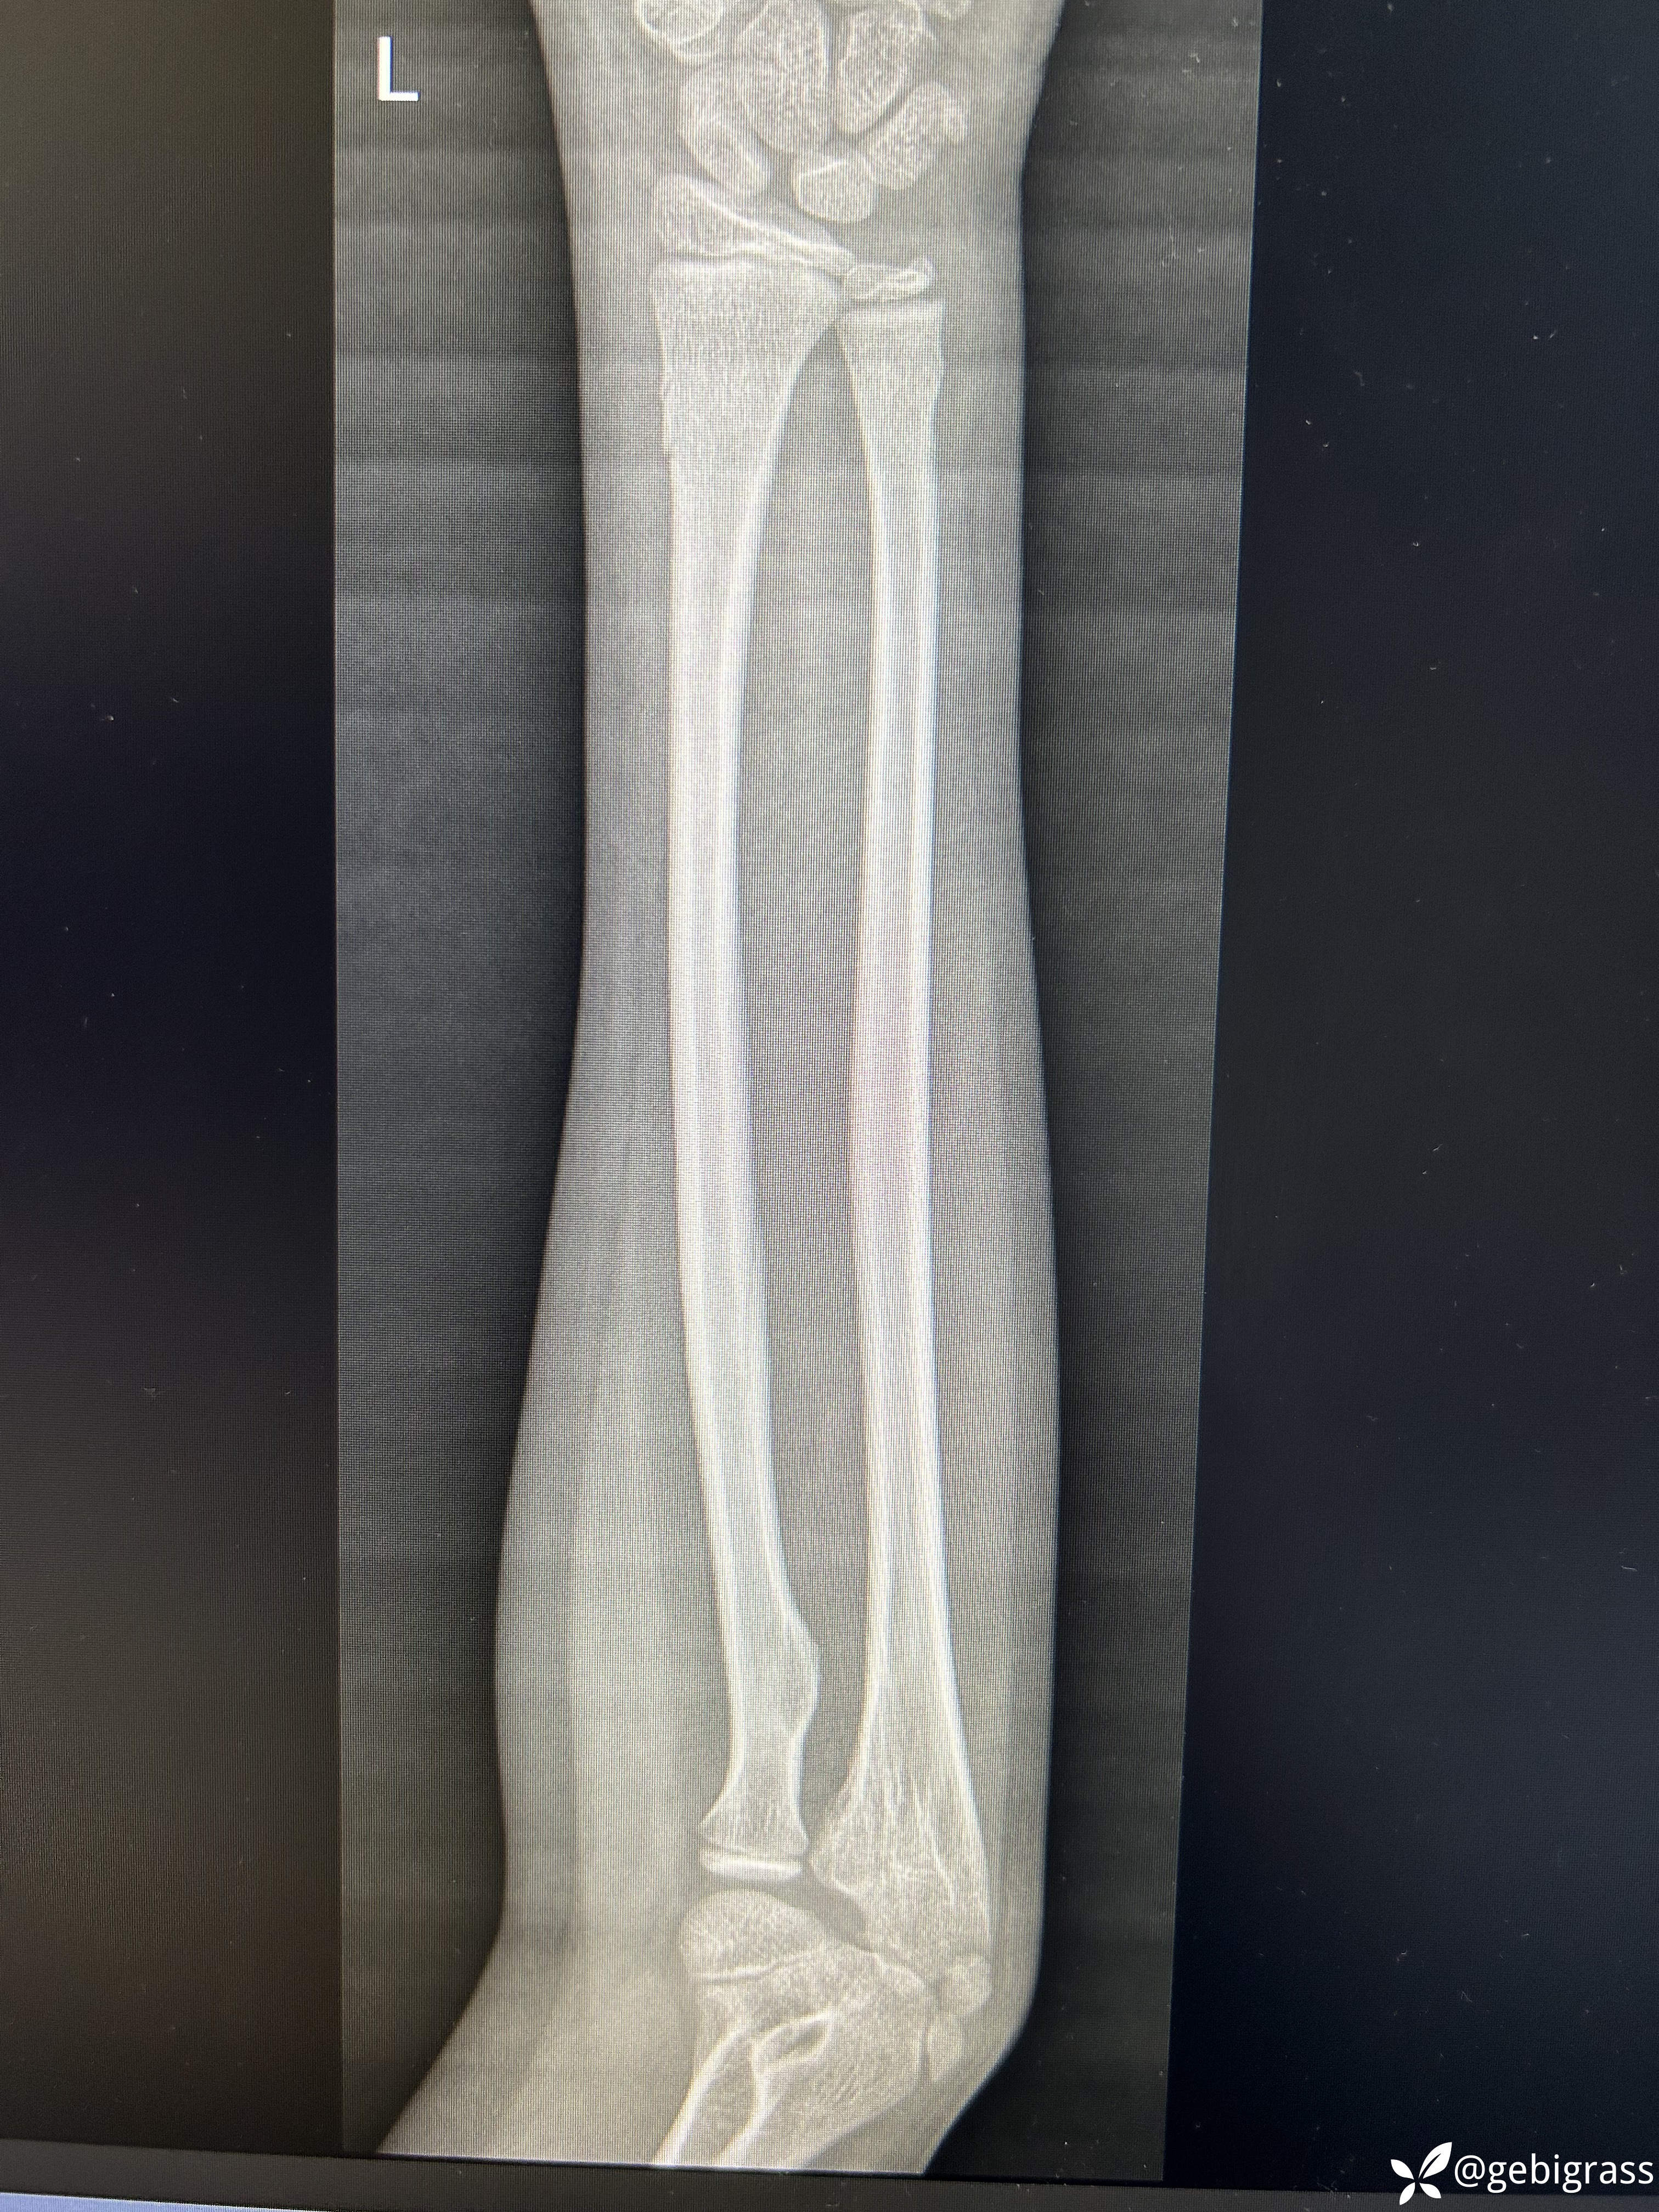

男,11岁,摔伤致左腕部疼痛活动受限1小时来院就诊,查体无神经症状。

入院拍片: